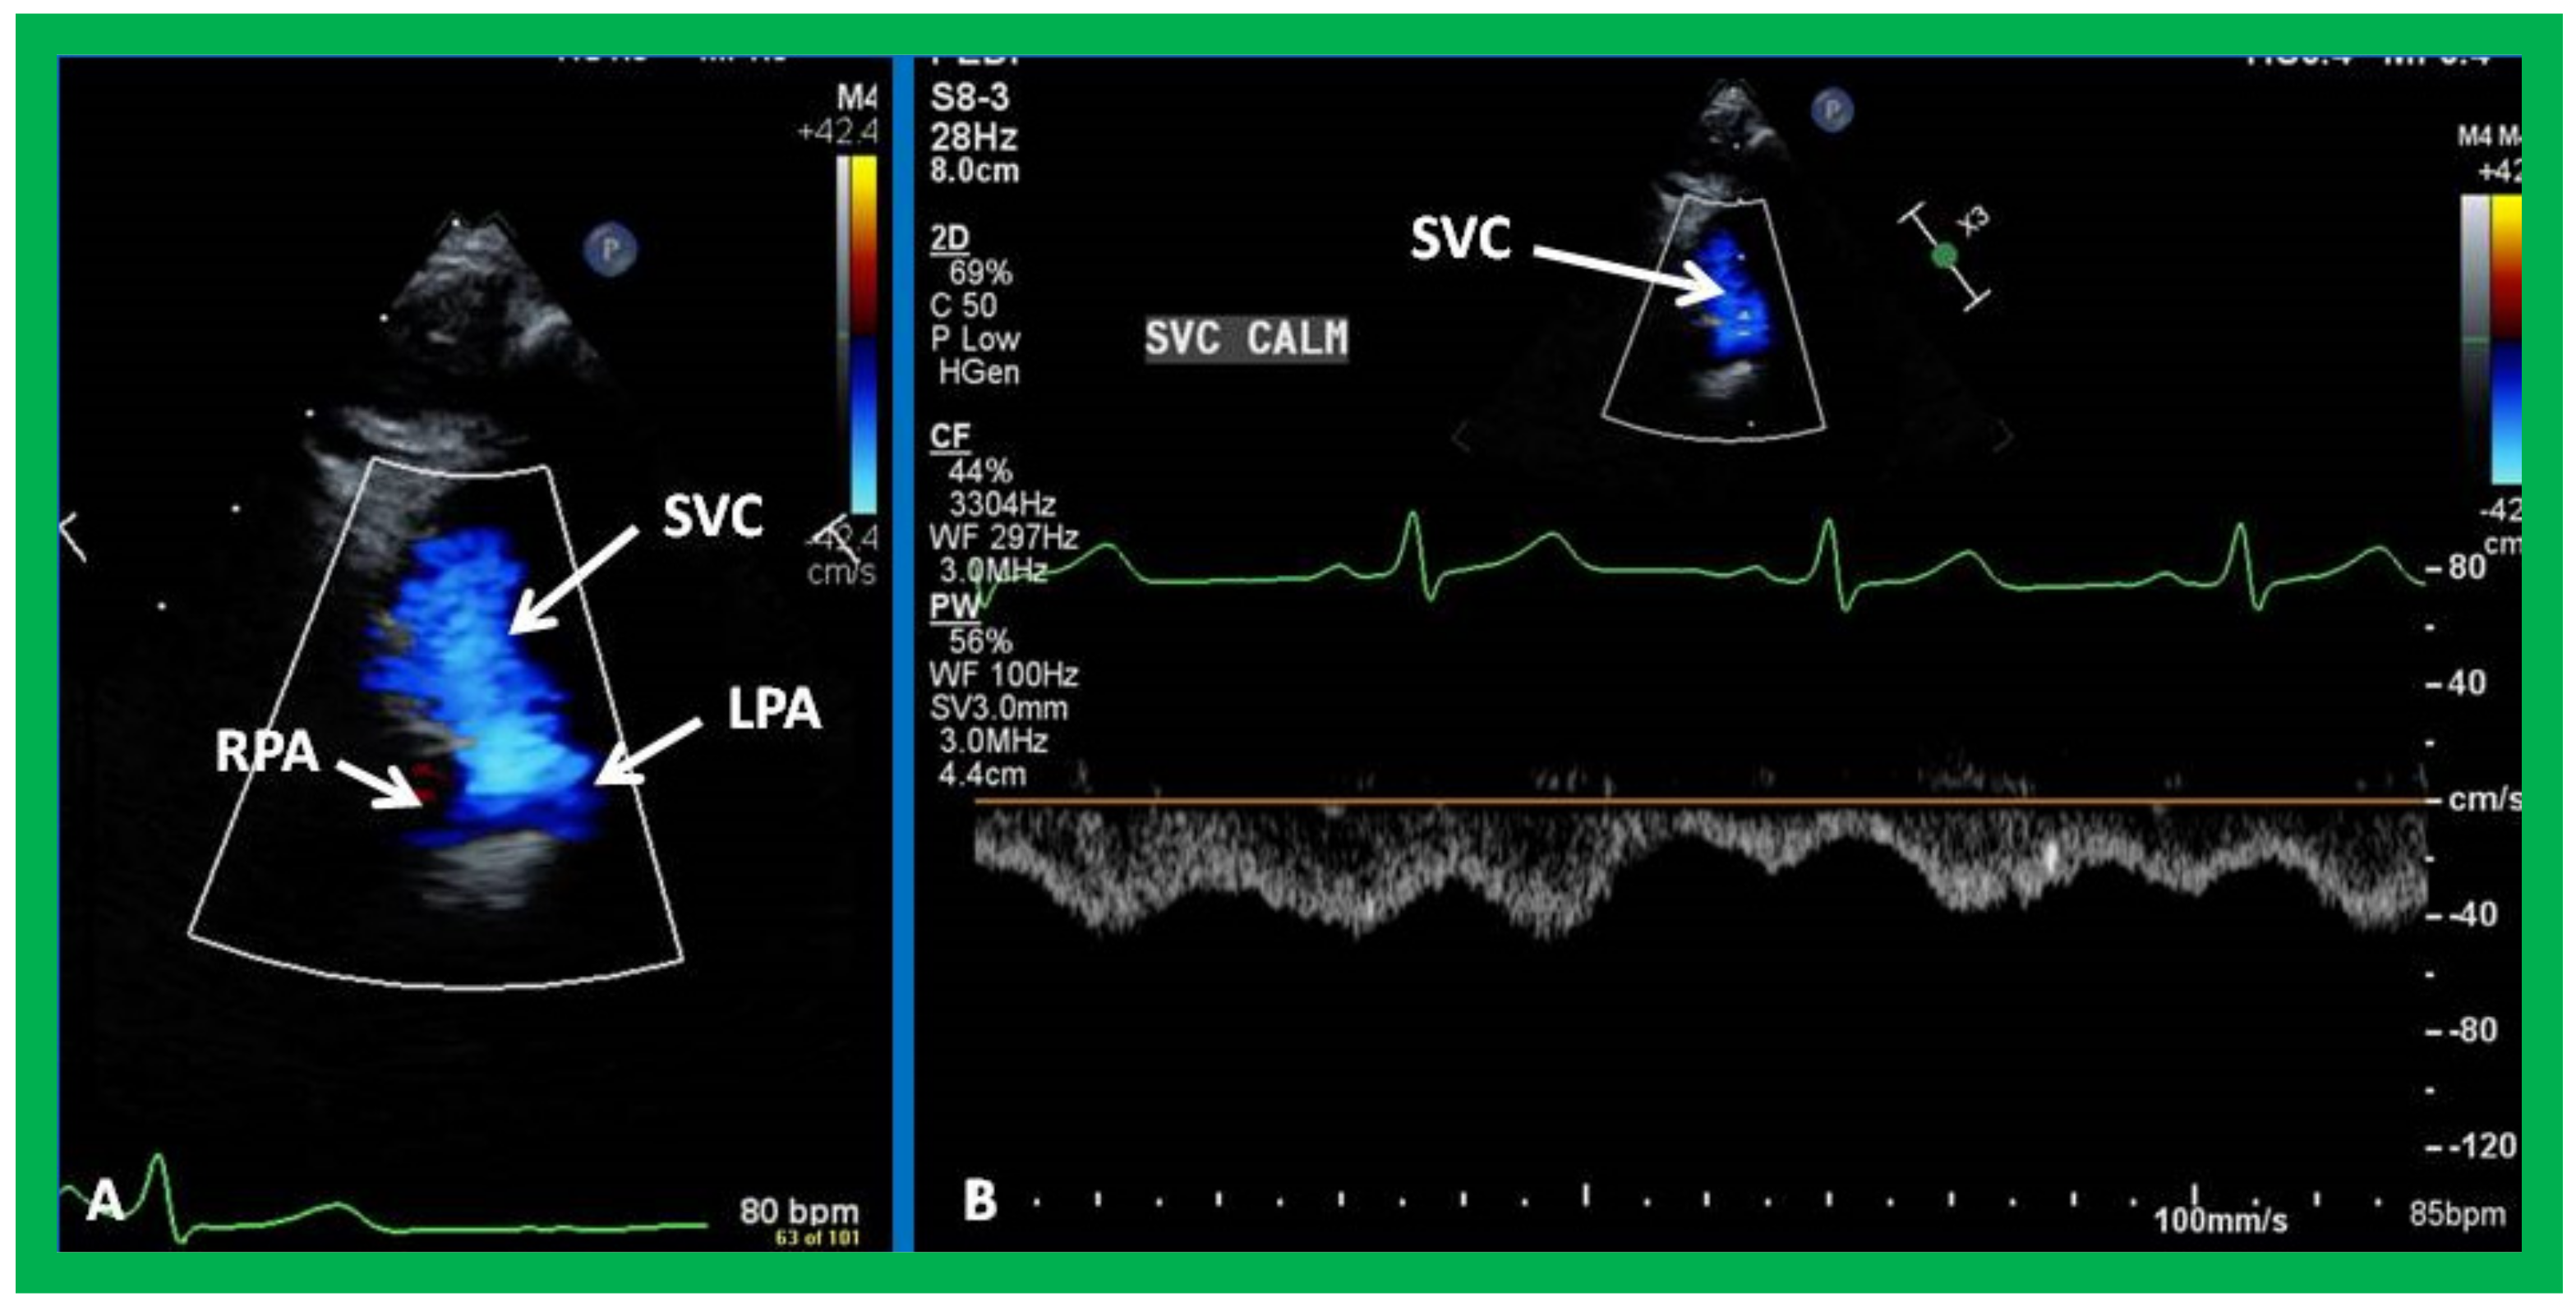

7. Echocardiogram